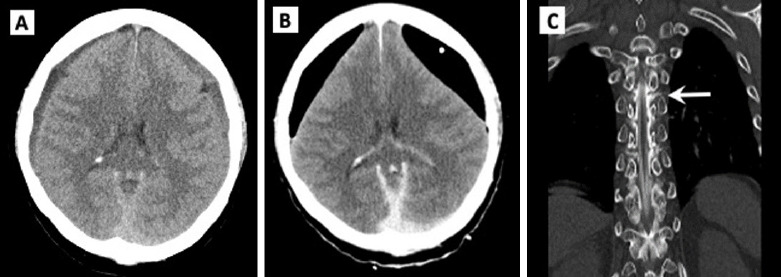

This case series highlights chronic subdural hematoma in previously healthy young and middle-aged patients, where symptoms persisted despite initial surgical intervention. Subsequent diagnosis revealed spontaneous intracranial hypotension through computed tomography myelography. All patients experienced symptom relief after undergoing epidural blood patch. In conclusion, spontaneous intracranial hypotension should be considered in chronic subdural hematoma cases without trauma or underlying disease, with epidural blood patch recommended before surgical intervention if spontaneous intracranial hypotension is suspected.

Abstract Image